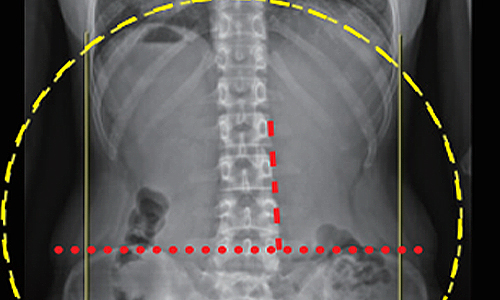

• 10대 학생

치료기간 1.5개월

BEFORE

AFTER